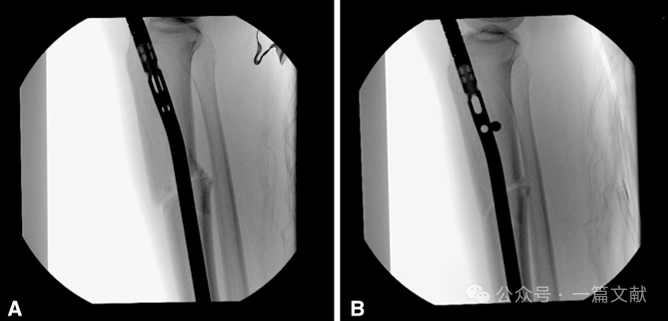

图1,髓内钉开口:(A) 在正位(AP)图上,导针位于胫骨外侧髁间棘的内侧。(B) 在侧位上,导针位于胫骨关节面的前缘,以避免损伤关节面或半月板,同时防止远端扩髓对胫骨结节和髌腱的影响。

图2,进针点的调整(双针技术):如果第一根针的位置不佳,可以将其保留作为参考,并适当的旋转套筒置入一根新导针,直到获得满意的进针点。在本例中,初始导针偏内侧,因此在外侧置入了一根新导针,使其在正位(AP)上刚好位于外侧胫骨髁间棘的内侧,同时在矢状面上保持相同的位置。这种方法有助于确保髓内钉的准确定位,从而提高手术的精确性和安全性。